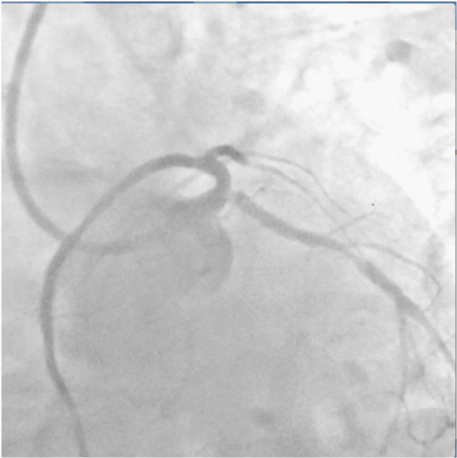

The patient was wheeled into the catch lab after pre-loading with 60mg Prasugrel and 300mg of Aspirin. He received 7,500units of unfractionated heparin and underwent coronary angiography from the right femoral route, which revealed 70% distal left main (LM) stenosis, and 70-80% ostial blocks of the left anterior descending (LAD) and left circumflex (LCX) arteries (Figures 2 & 3), (Video 1).The right coronary artery had a 50% stenosis at mid level (Figure 4). The patient was continuing to have chest pain despite prior administration of intra-venous morphine in the ER. He however was in a position to give informed consent for primary percutaneous intervention (PCI) subsequent to explaining that PCI would be a viable alternative keeping in view the urgency of intervention in his condition.

Figure 3 Spider view showing tight distal left main, ostial left anterior descending and ostial left circumflex arteries stenosis.